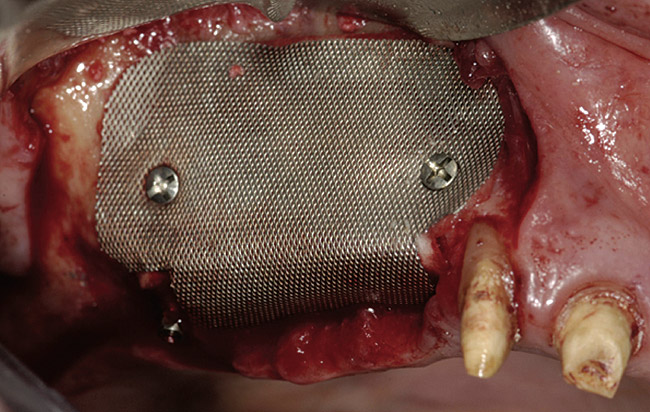

A 62-year-old woman was referred for fixed tooth replacement of the missing maxillary left cuspid, bicuspids, and first molar (Figure 11). Clinical and CBCT evaluation revealed an almost fully pneumatized maxillary left sinus along with alveolar width deficiency. The treatment plan called for a four-unit, implant-supported splinted fixed bridge. A left sinus augmentation along with a ridge split and interpositional bone graft consisting of rhBMP-2/ACS (INFUSE Bone Graft) and mineralized allograft (MinerOss) covered by a dense porous polyethylene mesh (Medpor®, Stryker, www.stryker.com) were done simultaneously (Figure 12, Figure 13 and Figure 14). Six months later, a follow-up CBCT revealed a well-incorporated graft with adequate bone volume and density for implant placement (Figure 15 and Figure 16). Final bridge fabrication followed 3 months later (Figure 17 and Figure 18).

Figure 14  High-density porous polyethylene mesh with fixation.

Figure 14

Figure 22  Titanium mesh fixation.

Figure 22